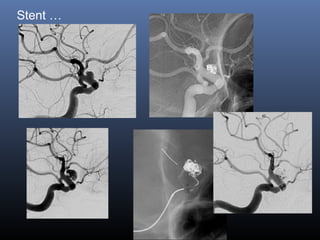

Stent …

 Flow modification

 Intimal growth and healing

 Change of angles

Issues

Persistent filling

Anti-platelet therapy in SAH

Single/double/flow divertor

Classical blister aneurysm

34-year M, SAH